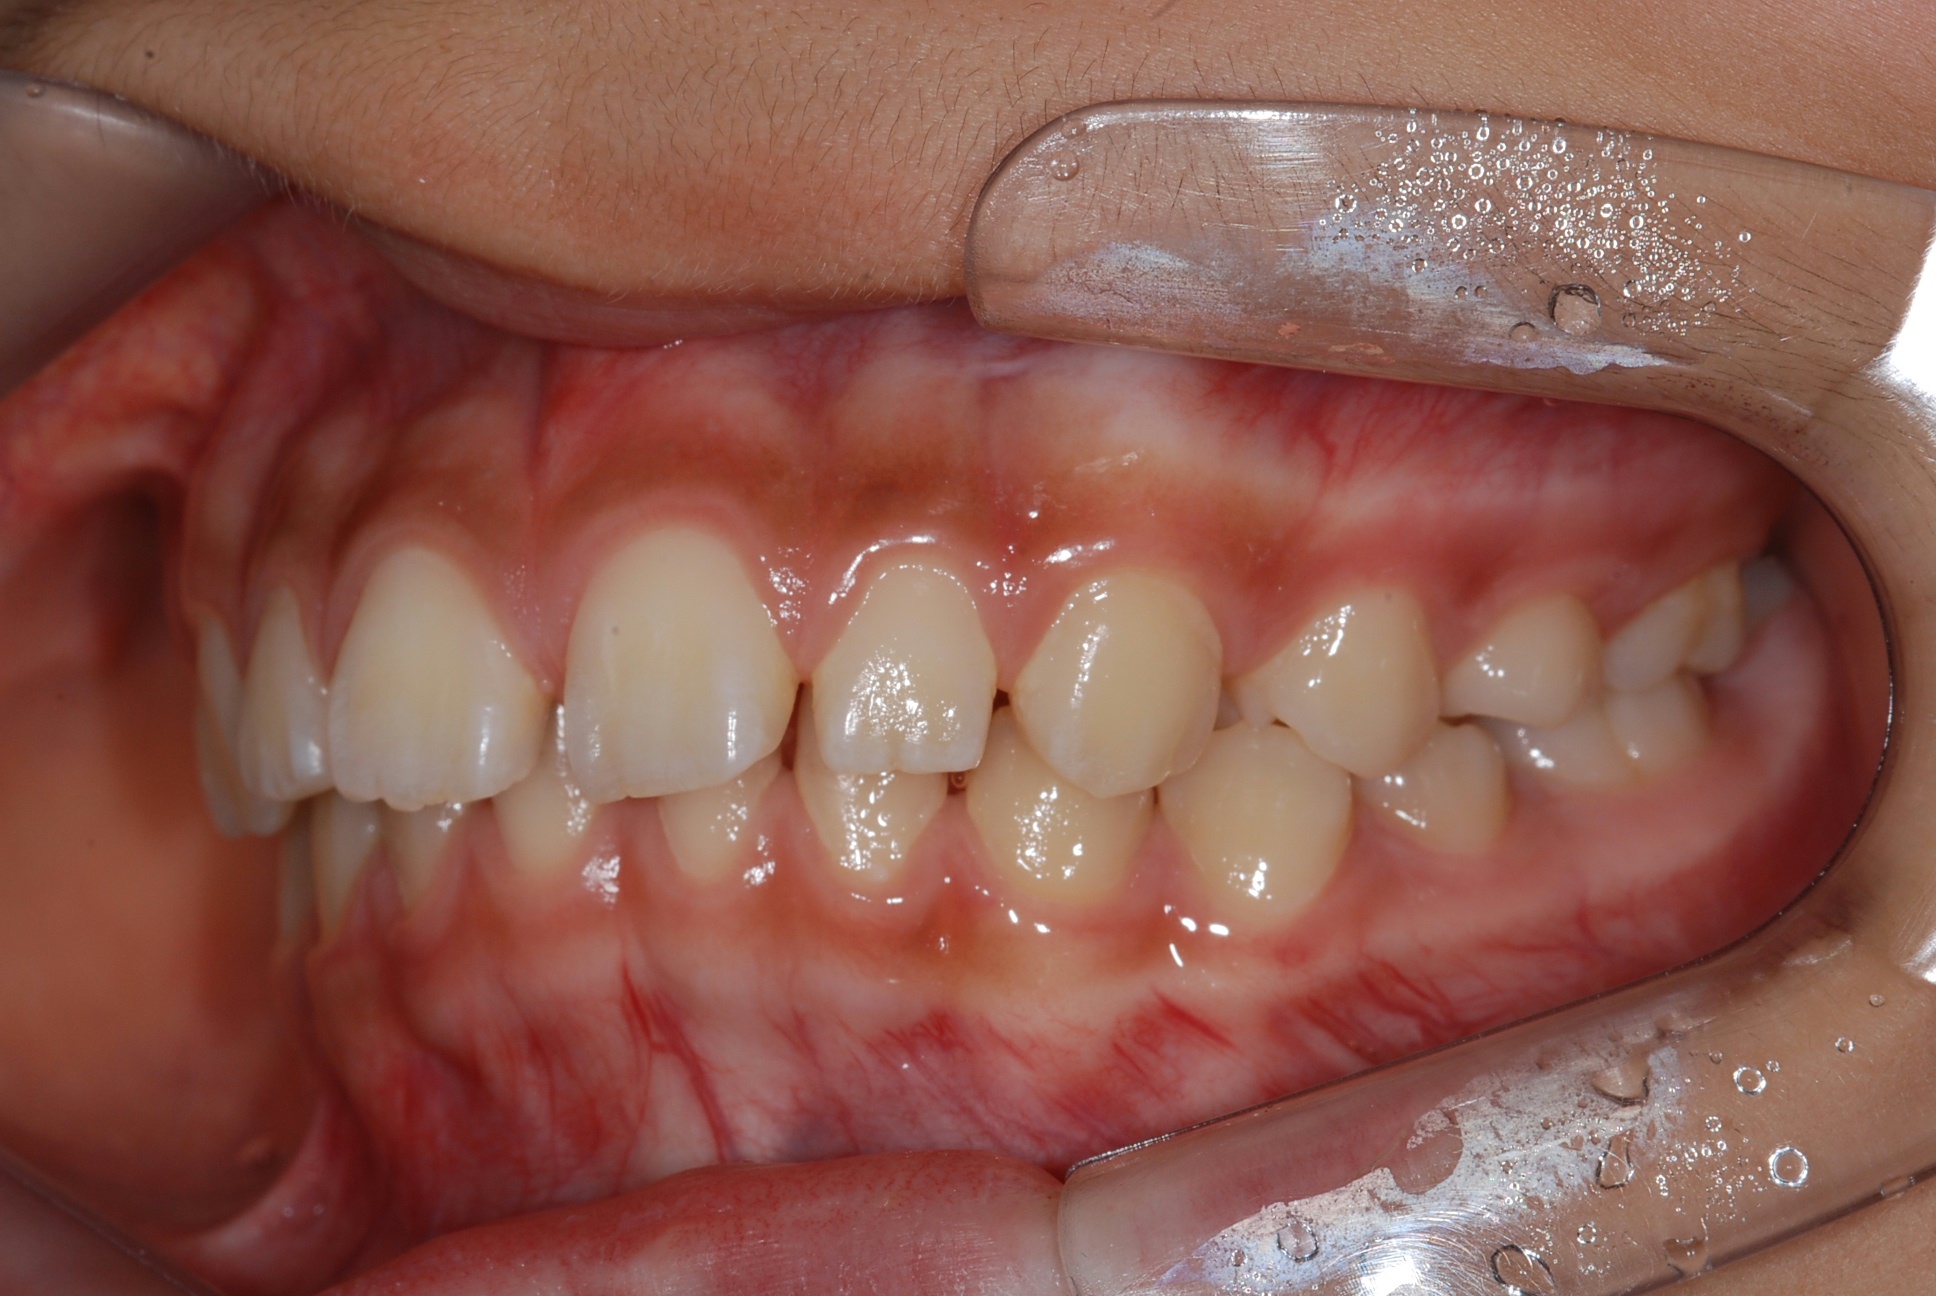

치료 전 사진입니다.